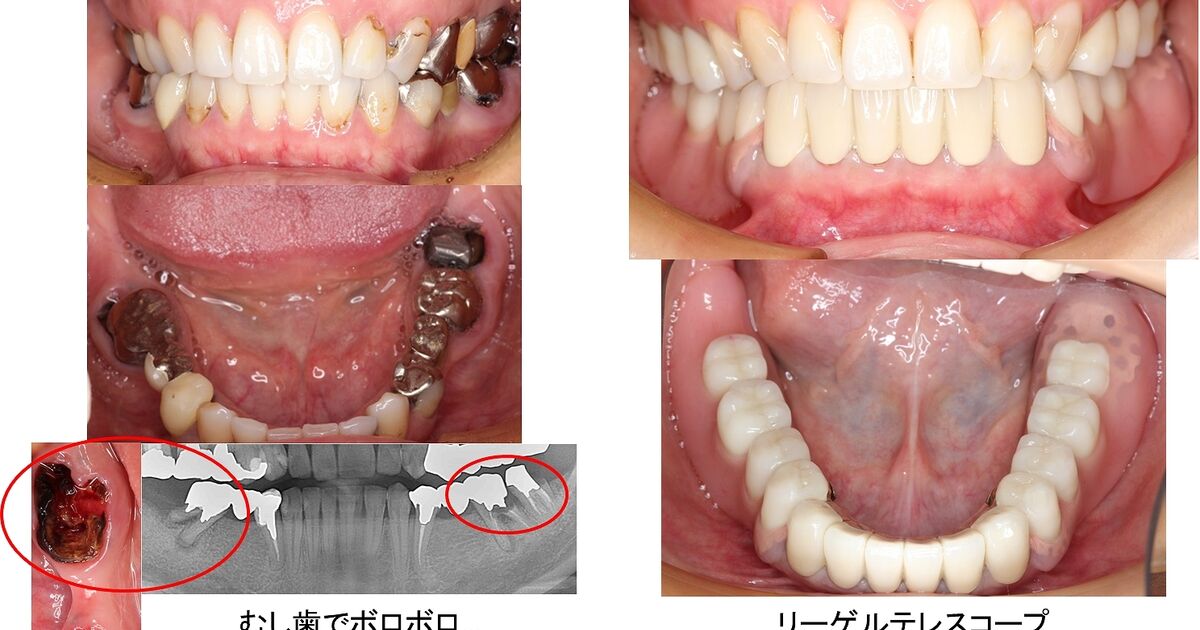

若い方の総入れ歯 東京都千代田区 稲葉歯科医院 総入れ歯専門サイト